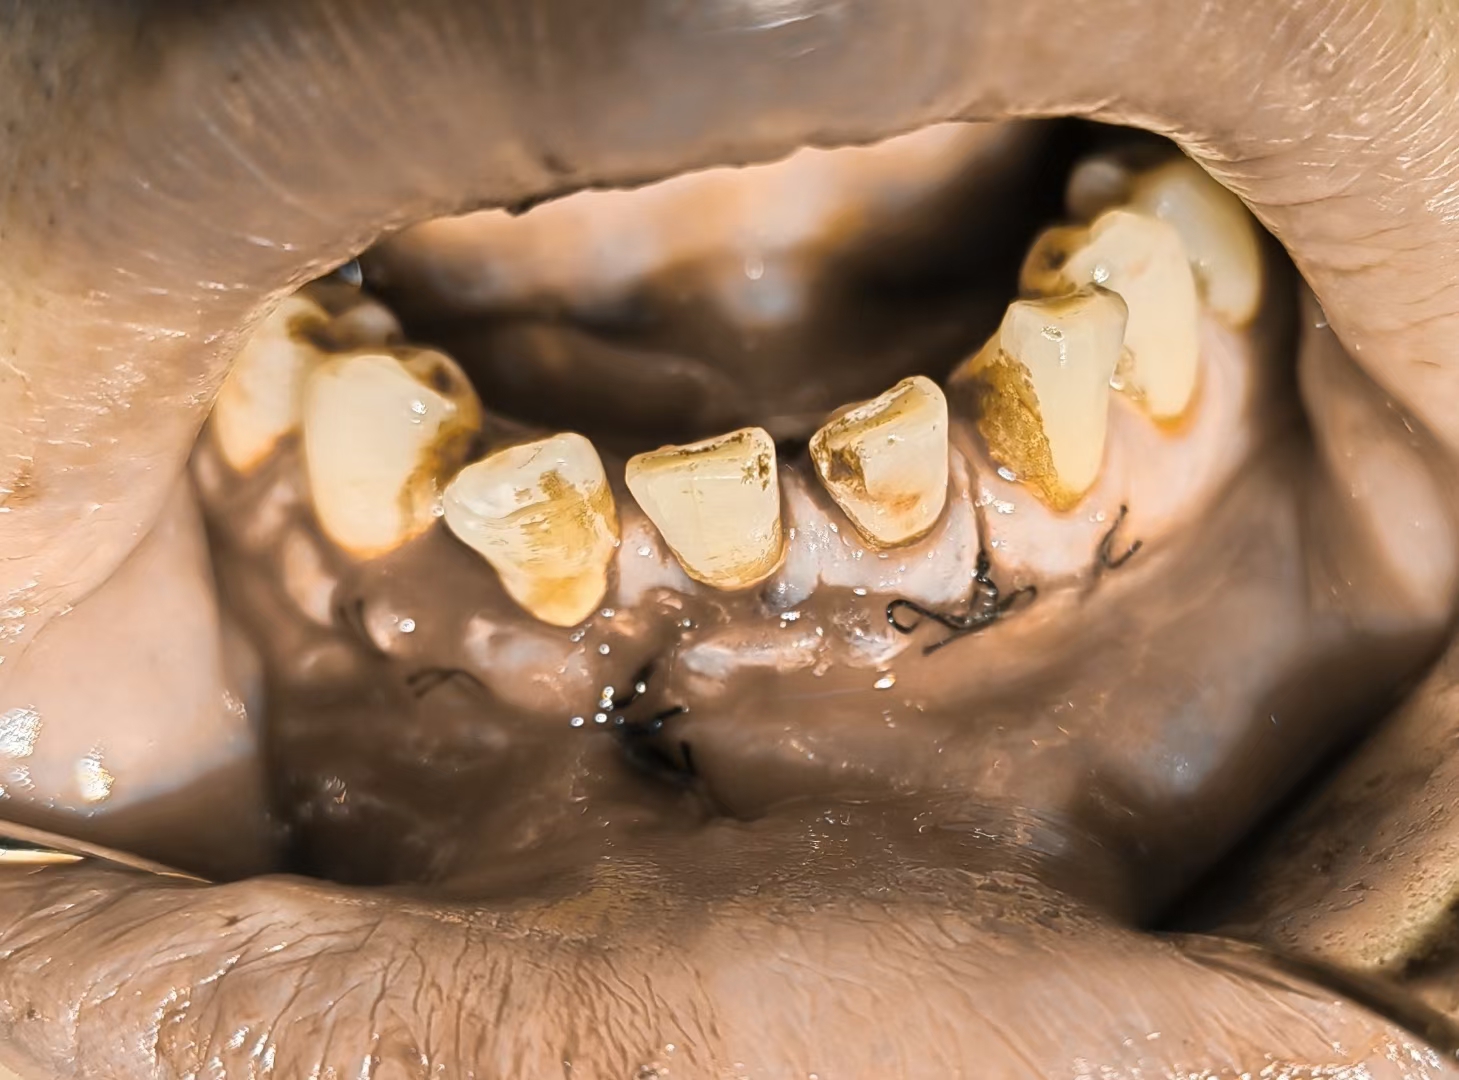

牙龈癌

牙龈癌,各种奇葩,无法描述